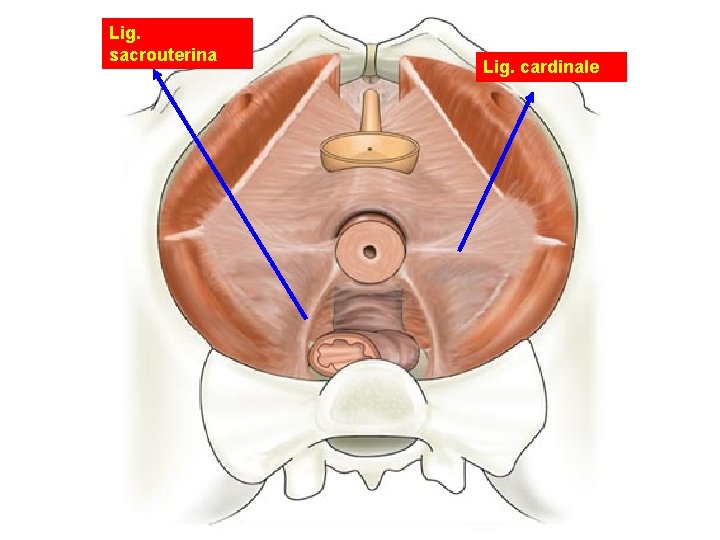

Lig. sacrouterina Lig. cardinale

Ligaments of the Uterus • Lig. Sacrouterinum (LUNA) • Lig. Latum Uteri • Lig. Rotundum – Cyst of Nuck canal – A. Sampson – Lig. Cardinale most important lig.